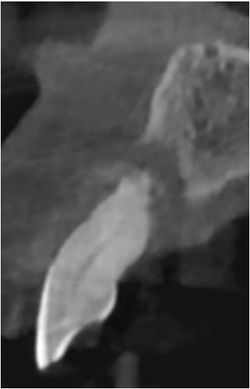

만일 발치 후 즉시 식립을 하기 위한 상기 조건들을 충족하지 못한 경우에는 발치와 보존술(socket preservation)을 통한 지연 식립이 일반적인 protocol로 권장됐고 순(협)측, 구개(설)측 골판의 골 소실이 50% 이상인 중등도 이상의 치주질환 [그림 1]의 경우 발치 후 즉시 식립 치료는 two-piece bone level 임플란트 시스템에 의한 식립의 한계로 인해 비적응증(contraindication)으로 인식돼 왔다.

중등도 이상의 치주질환에는 골결손은 있으나 연조직이 건재한 경우와 연조직 결손과 골 결손이 동반된 경우가 있다. 후자와 같이 광범위한 골 결손과 연조직 결손이 존재하는 경우에는 발치 후 즉시 식립의 예지성을 인정 받을 수 없기 때문에 일반적으로 지연 식립으로 치료했고 발치 후 치유 기간에 감소하는 골량(골 폭과 골 높이)으로 인한 불리한 식립 조건을 만나게 되면 이를 극복하고자 광범위한 박리 후 골유도재생술(Guided Bone Regeneration)로 치료했다.